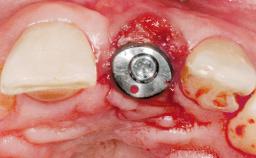

Immediate Flapless Placement of an Implant in a Maxillary Left Central Incisor Site

A 29-year-old female patient presented for treatment to replace the upper left central incisor tooth with an implant- supported restoration. The tooth had been intermittently symptomatic for the previous 12 months. The tooth had originally suffered trauma about 15 years previously. Several endodontic treatments had been performed, including an apicectomy procedure to retain the tooth. The patient was healthy and a non-smoker. She had reasonable expectations in regard to esthetic outcomes and the risk of marginal tissue recession following treatment. At medium smile, the gingival margins of the upper teeth were visible, with a display of 3 to 4 mm of the gingival margins. Gingival recession of tooth 21 and a discrepancy in the gingival levels between teeth 11 and 21 was observable during normal speech and smile.

Placement Protocol Immediate implant placement

Tooth Site Maxillary incisor or canine

Socket Morphology Single-root socket

Socket Integrity Damage to one or more bone walls